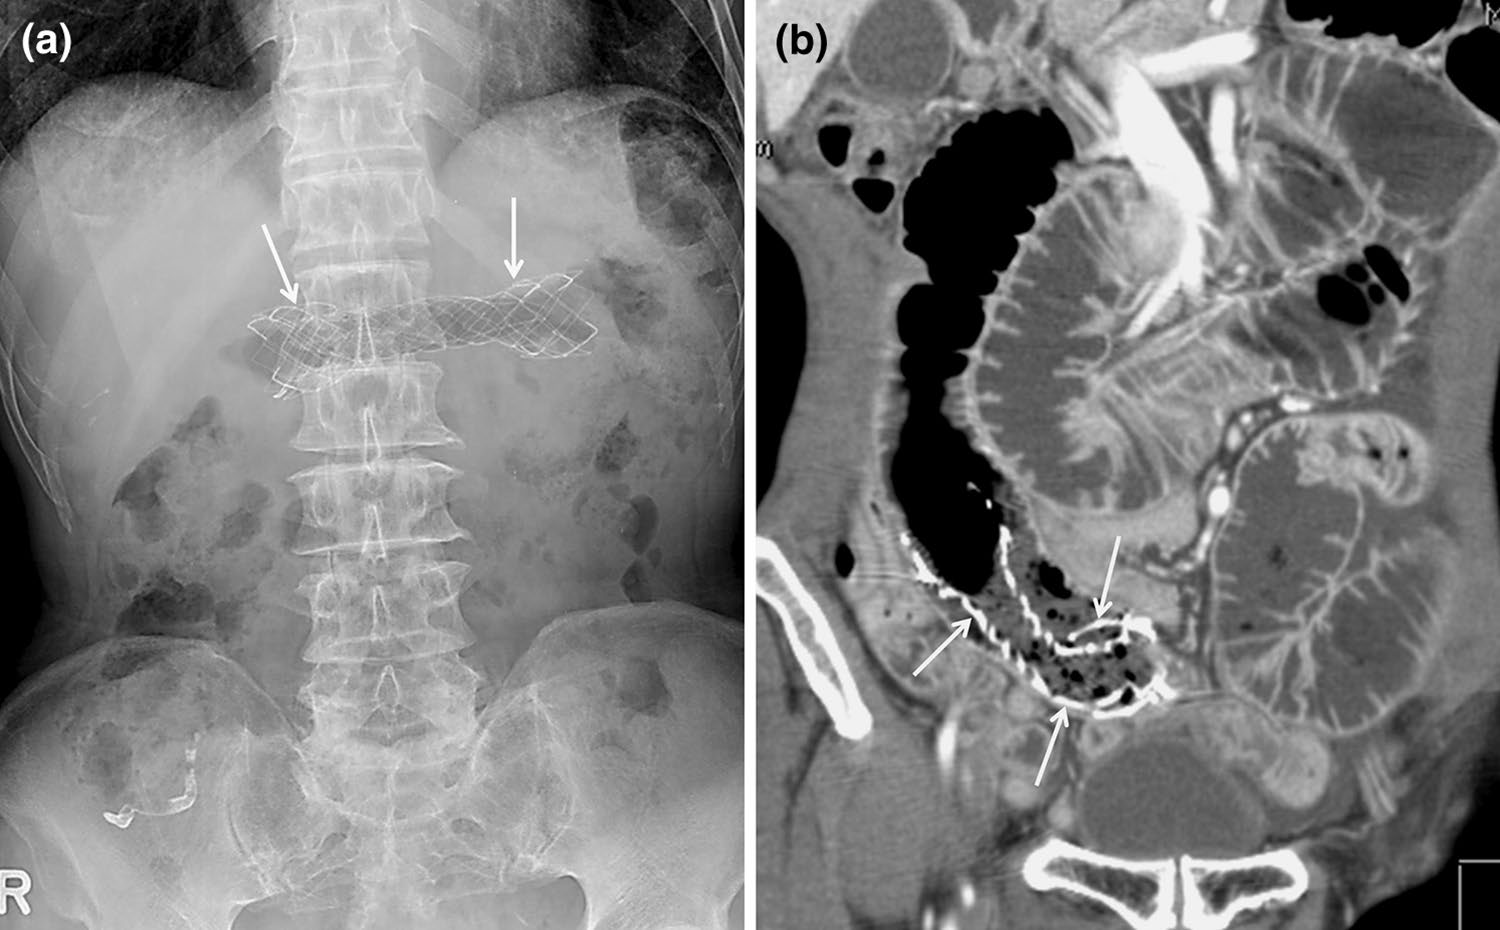

某些医疗器械的断裂可能与器械材料、植入时间、器械所处的解剖结构以及任何相关操作有关。支架断裂的报道发生率偏低,可能是由于意识不足以及对事件检测困难所致。胆道或胃肠道支架的断裂可能自发发生,也可能由用于治疗肿瘤再生的球囊扩张或氩等离子凝固引起(图16)[10]。这些断裂可能导致胃肠道出血、复发性胆道梗阻、肠梗阻或穿孔。

下腔静脉滤器已用于预防接受难治性抗凝治疗的患者发生危及生命的肺栓塞(图17)[1]。过滤器骨折的风险可能与过滤器在体内留置时间的长短有关,尽管报道的发生率约为5.5%;一项研究显示,在5.5年时的预测断裂率为40%(图18)[9]。此外,断裂碎片的迁移可导致危及生命的并发症。因此,如果不再需要防止肺栓子,应尽早考虑取出过滤器。